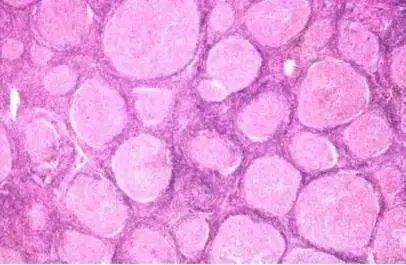

惰性淋巴瘤

对于惰性淋巴瘤,可选用的化疗单药有烷化剂如苯丁酸氮芥、环磷酰胺等药物,有效后停药观察。烷化剂对于进展期的慢性淋巴细胞性白血病(CLL)有肯定的效果。缺点是缓解率低,不能延长患者的生存期。氟达拉滨为核苷类似物中的一种,于20世纪80年代开始用于临床,标准用法为25~30毫克/平方米/天,共用3-5天,静滴,每1月为一个疗程。用于初治慢性淋巴细胞白血病患者的完全缓解率(CR)为38%,部分缓解率(PR)为60%,疗效优于既往其他药物,但是使用2周期如未达PR者,提示预后不佳。氟达拉滨的主要不良反应为:骨髓抑制和免疫抑制,应用后易并发各种条件致病菌感染,部分患者可并发自身免疫性溶血性贫血(AIHA)、免疫性血小板减少性紫癜(ITP)等,老年人使用氟达拉滨应更为慎重。

治疗惰性淋巴瘤的联合用药方案有FC(氟达拉滨+环磷酰胺)、FMD(氟达拉滨+米托蒽醌+地塞米松)、FN(氟达拉滨+米托蒽醌)、CVP(环磷酰胺+长春新碱+泼尼松)或CHOP(环磷酰胺+阿霉素+长春新碱+泼尼松)方案等。对于CD20阳性者,NCCN指南推荐化疗联合利妥昔单抗治疗,结果显示,患者在治疗12个月后其部分缓解率(PR)为89%,利妥昔单抗联合化疗使用可明显提高患者的疗效。目前,层出不穷的新分子靶向药物为治疗惰性淋巴瘤提供了新的选择,相应的临床研究也在如火如茶地进行。